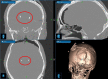

Images obtained from the DBS surgery planning station showing coronal (top left), sagittal (top right), and axial (bottom left) pre-operative MRI with an overlayed atlas to identify the STN based on high iron deposits (coloured MRI) and atlas anatomic identification. Bottom right image showing a 3D reconstruction with the planned bilateral electrode insertion trajectory

Post-operative, bone-window CT head images showing coronal (top left), sagittal (top right), and axial (bottom left) positioning of bilateral, STN DBS leads